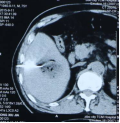

社会快速发展所带来的环境影响,让肿瘤离我们越来越近,当身边的人患有这种疾病时,给患者和亲人带来沉重的思想包袱,而开刀、化疗、放疗等传统治疗方式又给肉体带来更加痛苦的深层次打击。 患者往往对传统治疗望而却步,在绝望中等待生命的终结…… 问 还有希望吗!还有别的治疗方法吗? 答 有!而且还很易于接受。 一根细针,一根细细的PVC导管,或许就能给你带来希望。 通过细针,经皮穿刺病灶,取得细胞学、组织学等资料,可以让我们了解到底是恶性肿瘤还是良性疾病,并知道是什么类型的肿瘤;通过细针,可以让针尖加热,把肿瘤加热失去活性,就像把鸡蛋煮熟了再也孵不出小鸡那样,肿瘤就不再生长,而逐渐吸收变小;通过细针,可以把小小的粒子植入肿瘤,通过粒子缓慢释放能量,把肿瘤灭活,达到治愈肿瘤病灶的目的。 通过导管,进行血管造影进一步确认到底是不是恶性肿瘤;通过导管,并可把载有抗肿瘤药物微球直接注射进入肿瘤血管,缓慢持续长时间杀灭肿瘤细胞;通过导管,可以把给肿瘤供血的血管堵起来,让肿瘤失去血流,失去养料供给,饿死它。 上帝为你关上一扇门的同时,必定会为你打开了另一扇窗,快速发展的社会,科技日新月异,新技术新方法也给肿瘤治疗带来了新的希望。 近年来,淄博市中医医院介入科引入诸多新时代发展带来的前沿新技术,结合数千年古老神秘的中医调理,给诸多患者带来了新的希望和愉快的新生活。 病例一 2015.9 2015.9.11微波消融后 2017.4 肝动脉栓塞并粒子植入,病变直径75mm 2021.4.复查,病变直径35x23mm 病例二 2015.7 肝动脉栓塞并肝癌微波消融 2017.8 MRI复查,病变未见进展 2021.7 CT复查病灶显著缩小 患者后期按时复查,其他处有新增病灶,通过多次介入治疗,至今健在。 介入放射学 是在现代影像学(DSA、CT、超声、磁共振等)方法的引导下,采取经皮穿刺、插管,对患者进行血管造影、采集病理学、生理学、细胞学、生化学检查资料,进行药物灌注、血管栓塞或消融等"非外科手术"方法诊断和治疗多种疾病。 其特点简便、安全、有效、微创、可重复治疗和并发症少,该技术也适合肺癌、肾癌、胰腺癌、甲状腺结节、肺结节等疾病的治疗。 它将不能治疗的疾病变为可治疗、难治性疾病变为容易治疗、复杂治疗疾病变为简单治疗、大创伤治疗变为微创治疗、危险治疗疾病变为安全治疗。目前许多介入方法成为了主要的治疗方法,甚至取代或淘汰了原来的外科手术。 淄博市中医医院介入科 0533-6699127、6699128 官方微信公众号 长按关注 获取更多健康咨询 淄博市中医医院 淄博市中医医院始建于1952年,是鲁中地区最大的一所集医疗、科研、教学、养生保健四位一体的综合性三级甲等中医医院。是山东中医药大学的附属医院、国家住院医师规范化培训基地、山东省中医药预防保健服务中心。设有21个临床科室,9个医技辅助科室,开放床位700张。医院拥有核磁共振、CT等大型诊疗设备300多台件。 预约电话:0533-6699333、6433111 新院区地址:周村区新建东路1166号(碧桂园对面) 。 电话:0533-6699333、6433111 1.乘坐96路公交车到碧桂园站下车 2.乘坐291路公交车到碧桂园站下车 3.乘坐258路公交车到碧桂园站下车 老院区地址:山东省淄博市周村区新建中路75号(乘坐238路、239路、34路、96路公交车均可到达) 和平路院区地址:张店区和平路18号(南西五路与和平路转盘东北角) 电话:0533-2210092 1.乘坐35路、121路、132路、95路公交车和平小区站下车北行100米即到。 2.乘坐138路、223路公交车天星小区站下车东行200米即到。 3.乘坐96路、126路、12路公交车中国陶瓷馆站下车南行600米即到。官方抖音